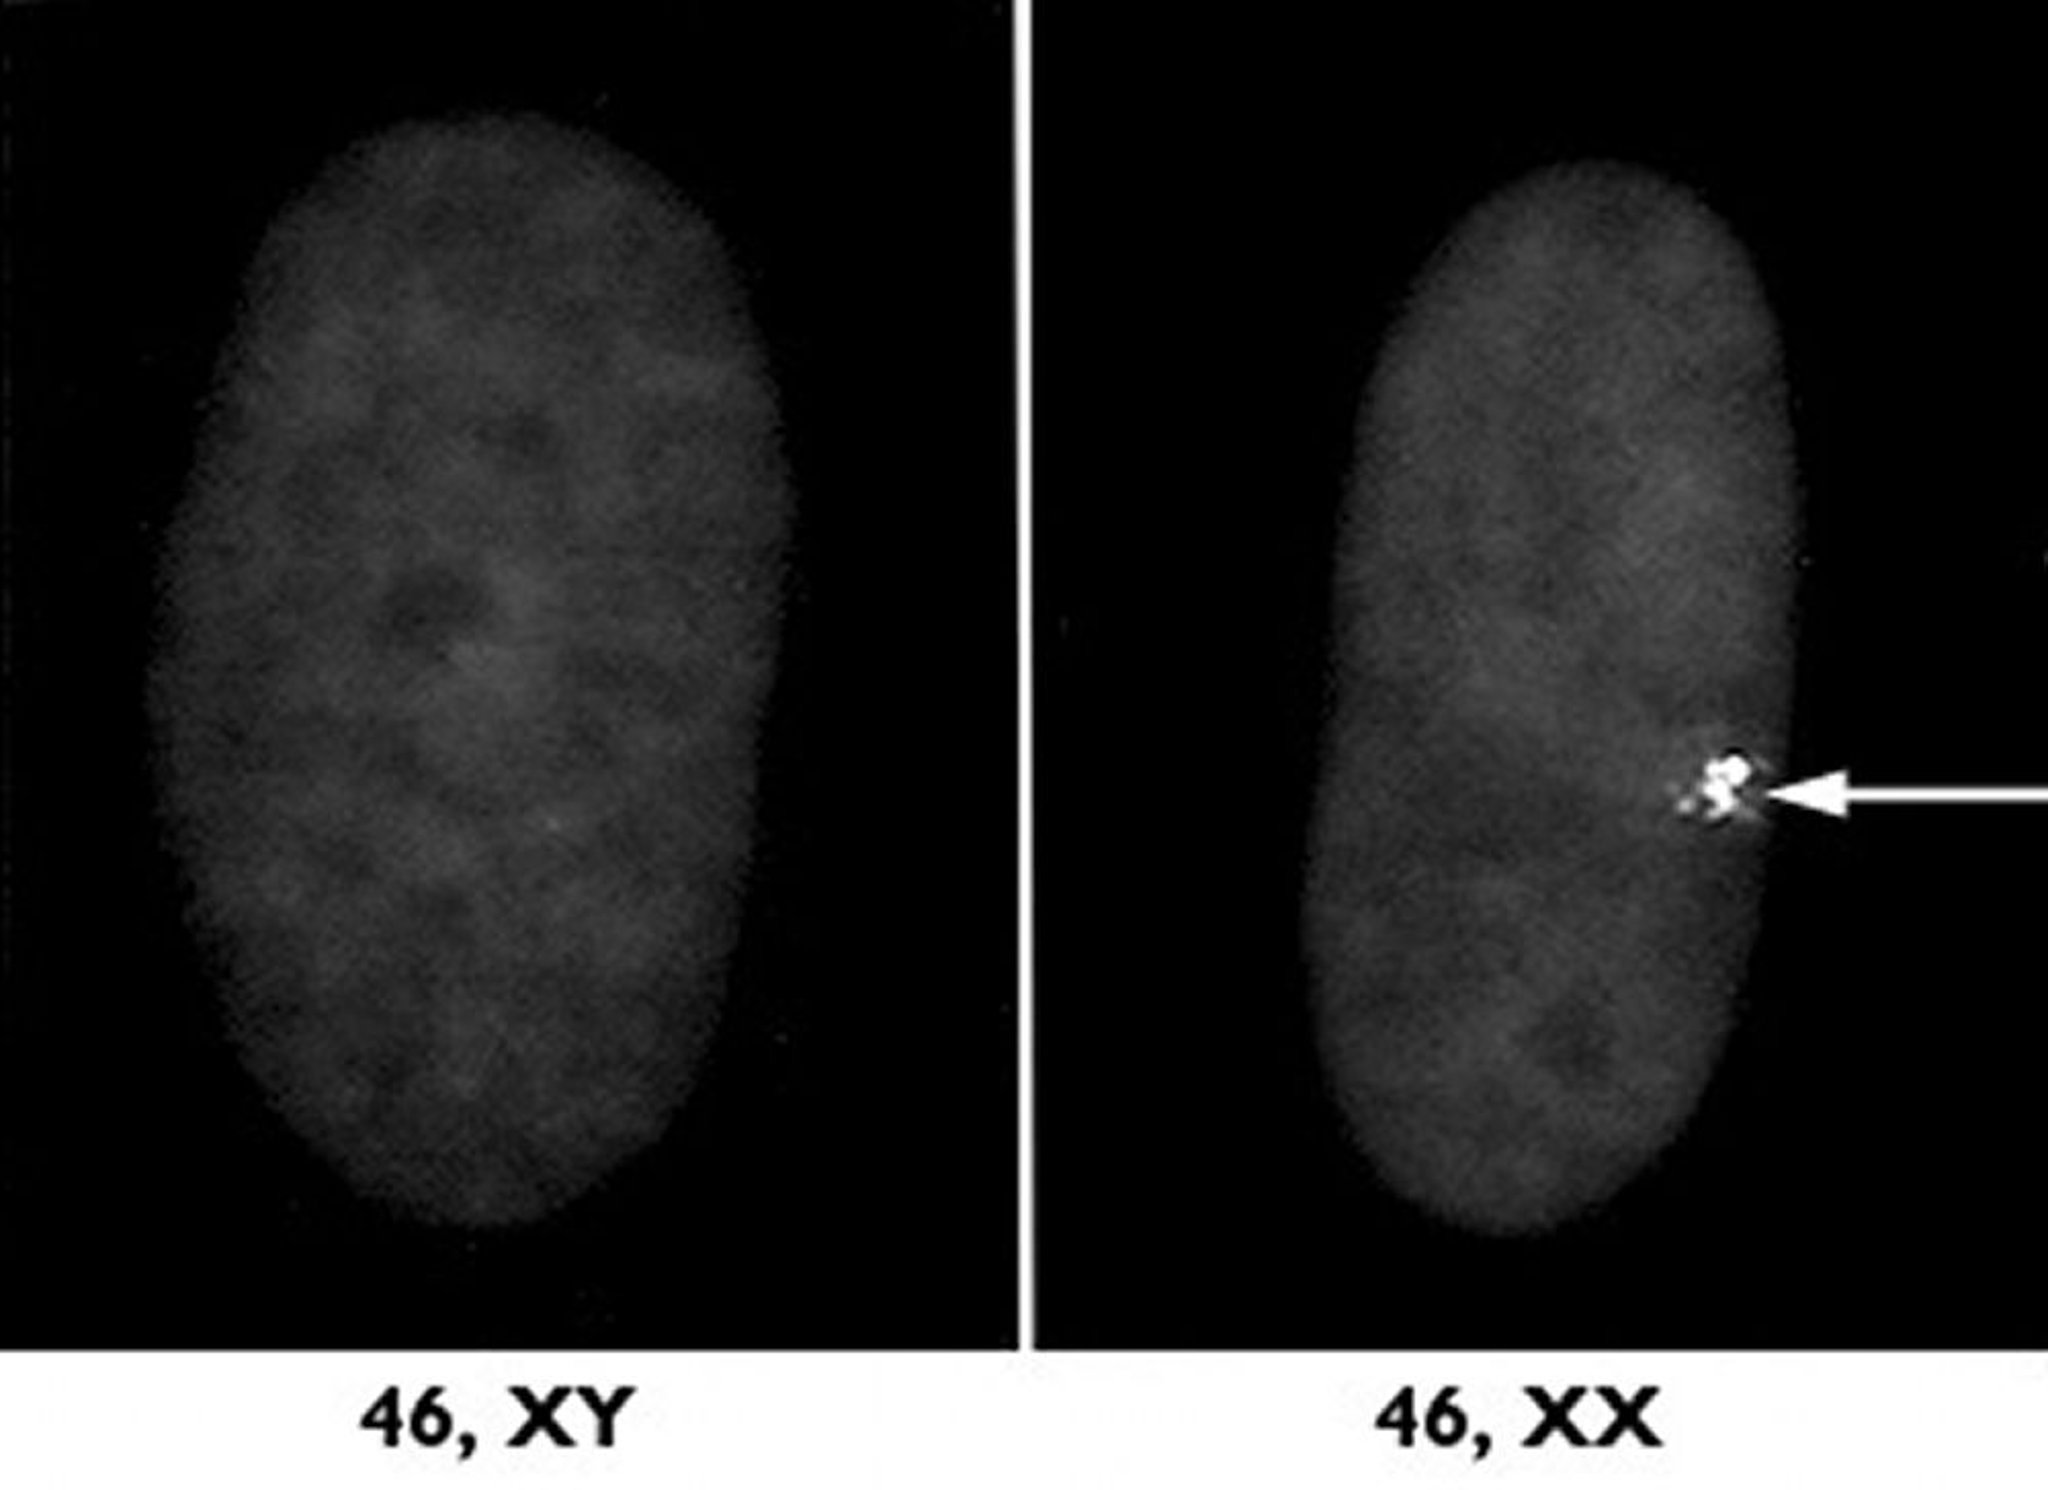

cromosoma X inattivo

Uno dei due cromosomi X nelle donne è disattivato attraverso un processo che prende il nome di inattivazione del cromosoma X. A destra, un campione microscopico di un nucleo cellulare di un soggetto di sesso femminile mostra questo cromosoma X inattivo come nodulo denso (freccia). A sinistra è raffigurato un campione relativo a un individuo di sesso maschile per raffronto.

Per gentile concessione di Carrell e H. Williard, Case Western Reserve University School of Medicine.